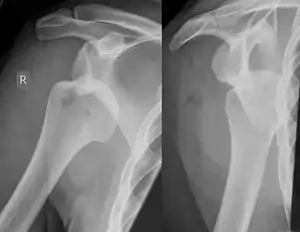

A Hill–Sachs lesion, or Hill–Sachs fracture, is a cortical depression in the posterolateral head of the humerus. It results from forceful impaction of the humeral head against the anteroinferior glenoid rim when the shoulder is dislocated anteriorly.

Diagnosis can be suspected by history and physical examination which is usually followed by imaging. Because of the mechanism of injury, apprehension of anterior dislocation is common with provocative maneuvers. Hill–Sachs lesions have been classified as "engaging" or "non-engaging", with engaging lesions defined by the ability of the glenoid to sublux into the humeral head defect during abduction and external rotation. Engaging dislocations have a higher risk of recurrent anterior dislocation, and their presence can help guide surgical management.[2] Imaging diagnosis conventionally begins with plain film radiography. Generally, anteroposterior (AP) radiographs of the shoulder with the arm in internal rotation offer the best yield while axillary views and AP radiographs with external rotation tend to obscure the defect. However, pain and tenderness in the injured joint make appropriate positioning difficult and in a recent study of plain film x-ray for Hill–Sachs lesions, the sensitivity was only about 20%. i.e. the finding was not visible on plain film x-ray about 80% of the time.[3]

The incidence of Hill–Sachs lesion is not known with certainty. It has been reported to be present in 40% to 90% of patients presenting with anterior shoulder instability, that is subluxation or dislocation.[8][9] In those who have recurrent events, it may be as high as 100%.[10] Its presence is a specific sign of dislocation and can thus be used as an indicator that dislocation has occurred even if the joint has since regained its normal alignment. Large, engaging Hill-Sachs fractures can contribute to shoulder instability and will often cause painful clicking, catching, or popping. The average depth of Hill–Sachs lesion has been reported as 4.1 mm.[11]